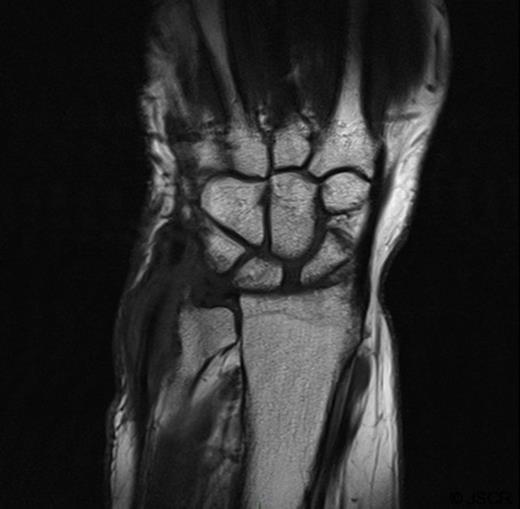

She presented again at the orthopaedic clinic 26 months later with continuing swelling and pain. Ultrasound showed a synovial tumour on the dorso-medial aspect of the wrist (Figure 1). Aspiration of the cyst produced a small amount of pus. She was admitted for incision and drainage of the abscess. Microscopy of the tissue showed a granulomatous inflammation.

Ultrasound showing a synovial tumour on the dorsal medial aspect of the wrist